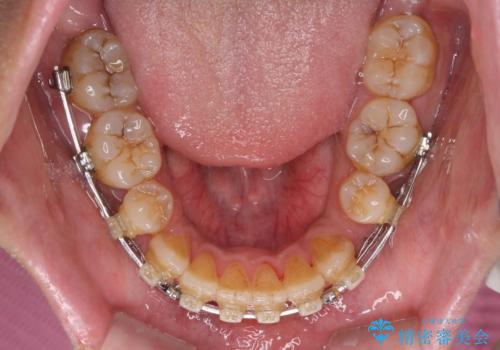

- クリアブラケット

- 2年6ヶ月

- 10-30回

舌の突出癖を改善するためのトレーニングを指導していましたが、なかなか改善することができず、ワイヤー装置を外してからも上下前歯に隙間ができやすい状況でした。